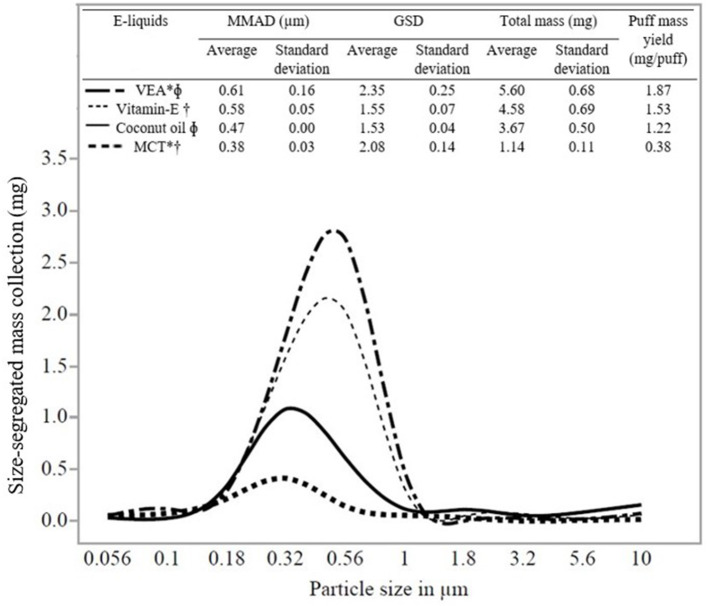

Figure 2 shows a representative particle size distribution (in the x-axis) and size-segregated mass (mg) deposition (in the y-axis) for all the e-liquids evaluated in the study. The average MMAD and standard deviation for five trials evaluating e-liquids were as follows: Vitamin E containing e-liquids (VEA: 0.61 ± 0.16 μm) and Vitamin E oil (0.58 ± 0.05 μm) and without Vitamin E containing e-liquids (coconut oil: 0.47 ± 0.00 μm) and MCT (0.38 ± 0.03 μm). One-way ANOVA (p = 0.0012) and Tukey’s test resulted in a statistically significant difference (at p < 0.05) between the MMADs for VEA and MCT, VEA, and coconut oil, and Vitamin E oil and MCT (Supplementary Table S2). However, we detected no significant statistical difference between the MMADs of VEA and Vitamin E oil (p = 0.24). Additionally, there was a wider aerosol size distribution emitted by e-liquids for VEA (GSD 2.35) and MCT (GSD 2.08) compared with coconut oil (GSD 1.53) and Vitamin E oil (GSD 1.55). Results of MMAD and GSD values for individual trials for all the e-liquids are presented in Supplementary Table S1.

Data (average, standard deviation for n = 5) in Figure 2 shows the total mass and puff mass yield (mg/puff) of EVP aerosol emitted by all the e-liquids. We found that both these attributes correlated with the MMADs of the e-liquids. MMAD of VEA was the largest (0.61 μm) and resulted in the highest averaged total mass collected and puff mass yield for VEA (5.60 mg) compared with other e-liquids. Additionally, VEA and Vitamin E oil (VEA at 5.60 mg and Vitamin E oil at 4.58 mg) resulted in the comparable total mass collection and puff mass yield (VEA: 1.87 mg/puff and Vitamin E oil: 1.53 mg/puff). Because of the potential hygroscopic nature of VEA particles, larger-sized EVP aerosols have more condensable material available for particle mass-growth, which corresponds well with the finding of the higher mass collection with larger MMAD (ref. 23, ref. 24, ref. 37, ref. 38). MCT and coconut oil aerosolized into smaller particles and because they have lower liquid densities (relative to VEA and vitamin E oil), they resulted in comparably less mass collection. The results of mass collection for the individual trials for all the e-liquids are presented in Supplementary Table S1.

Variations in EVP aerosol generation and characterization methods have led to a lack of reproducibility. Therefore, the ability to compare various studies or to integrate information is difficult (ref. 44–ref. 46). The puff-based mass collection presented in this study was an attempt to compare the results between existing studies within the given experimental parameters. Using the same type of cascade impactor, (ref. 37) found size distributions of two commercial e-cigs comparable to the size distributions measured by Ingebrethsen et al. (ref. 38) using spectral extinction with a slightly variable puff topography. As presented in Figure 2, we observed a similar trend between MMAD and mass collected for all the studied e-liquids. For VEA with MMAD of 0.61 μm, puff mass yield resulted in 1.87 mg/puff, which is comparable with the study of Alderman et al. results for one commercially available e-cig with MMAD of 0.63 μm that yielded puff mass of 2.16 mg/puff. Apart from different experimental parameters and sampling methods, differences were noticed in puff-mass measurements between these two studies for the same EVP devices. It was also hypothesized that the possibility of growth for larger-sized particles resulted in more mass collection. Similar to the study of Alderman et al., we observed more mass collection [Puff mass yield: VEA (1.87 mg/puff), vitamin E oil (1.53 mg/puff), coconut oil (1.22 mg/puff), and MCT (0.38 mg/puff)] for larger MMAD [VEA (0.61 μm), vitamin E oil (0.58 μm), coconut oil (0.47 μm), and MCT (0.38 μm)] of diluent oils, respectively. Our laboratory-prepared e-liquids included common diluent oils but not polypropylene glycol (PG), vegetable glycerin (VG), or nicotine. Particle size distribution of EVP aerosol depends on e-liquid compositions. This being one of the first studies to address the mass-based direct measurement of the particle size distribution for diluent oils, it is important to present the information in a way that could be compared with further research considering different experimental parameters. Moreover, by considering the accurate measurement of native particle size as close as possible, we provided conceptual estimates for deposition fraction and modeled per puff mass–dose deposition.